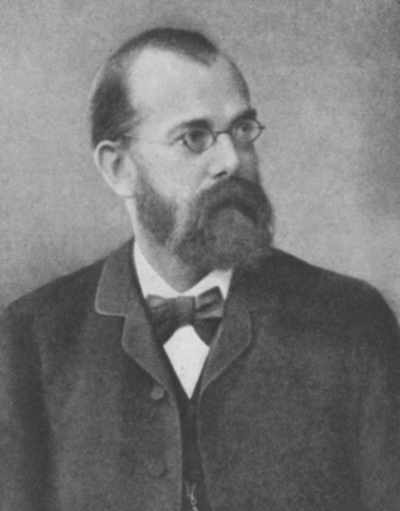

1890年

Robert Koch提出了特定微生物引起特定疾病的诊断要点,后来被称作"科赫法则(Koch's postulates)",经过一些修订,传染病教科书中至今还介绍这个法则。